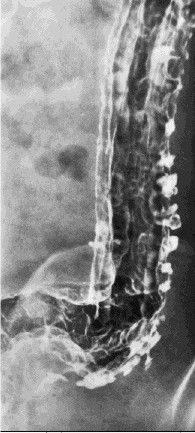

При смешивании крови, взятой у разных людей, часто происходит агглютинация (склеивание) эритроцитов в результате реакции антиген - антитело . В мембрану эритроцитов встроен целый ряд специфических полисахаридно - аминокислотных комплексов, обладающих антигенными свойствами. Эти комплексы называются агглютиногенами ( гемагглютиногенами ). С ними реагируют специфические антитела, растворенные в плазме , принадлежащие к фракции гамма - глобулинов - агглютинины ( изогеммагглютинины ). Предполагают, что при реакции антиген - антитело молекула антитела , обладающая двумя центрами связывания, образует мостик между двумя эритроцитами , каждый из которых в свою очередь связывается с другими эритроцитами, в результате чего происходит их склеивание. В норме в крови нет агглютининов к собственным эритроцитам.